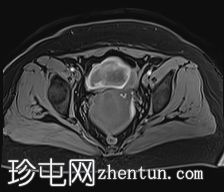

冠状位

T2加权像

可见子宫外腹腔内妊娠囊,内含胎儿组织。

该妊娠囊向后推移子宫,并与剖宫产瘢痕凹陷处紧密相连。

该妊娠囊与相关肠袢无法分离。可见其与性腺血管密不可分,且性腺血管明显突出。

胎盘位于妊娠囊后方,紧贴子宫前壁。

沿妊娠囊下缘可见一处异质性局灶性积液,最大轴向尺寸约为 8.4 × 5.5 cm,T1 加权像呈异质性高信号,T2 加权像呈异质性中等信号,T1 脂肪抑制序列未见信号下降,提示为血液成分。该积液压迫膀胱。

可见周围脂肪间隙呈条索状改变。

左侧卵巢无法辨认。

右侧卵巢未见实性或囊性肿块。

子宫体积增大,后倾,子宫内膜厚度约 1 cm,子宫下段前壁可见局灶性变薄(既往子宫瘢痕)。子宫连接区完整,未见肌层肿块。可见子宫内膜腔边缘有血性分泌物。